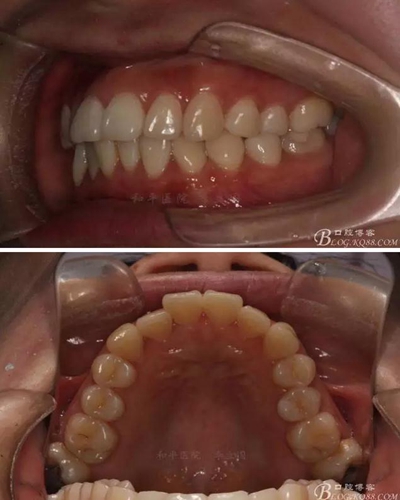

該病例主要為17、27頰側(cè)位同時(shí)伴有伸長(zhǎng),當(dāng)然種植支抗可以解決,但還有簡(jiǎn)單實(shí)用的辦法嗎?如圖,在橫腭桿遠(yuǎn)中延伸出牽引鉤,位置盡量遠(yuǎn)離合平面,7粘舌側(cè)扣,牽引力的方向?yàn)閴旱图吧嘞?,下圖為兩個(gè)月的效果,17已到位,27還未到位。